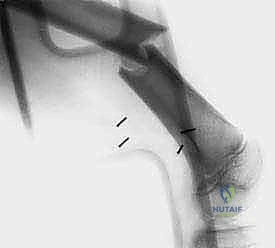

- الأشعة السينية (X-ray): الخطوة الأولى لتقييم العظام وتحديد نمط التدمير العظمي.

- الرنين المغناطيسي (MRI): هو المعيار الذهبي (Gold Standard) لتقييم الأورام. يوضح بدقة امتداد الورم في النخاع العظمي والأنسجة الرخوة، وعلاقته بالأعصاب والأوعية الدموية.

- الأشعة المقطعية (CT Scan): ضرورية لتقييم القشرة العظمية والتكلسات داخل الورم، وللبحث عن أي انتشار في الرئتين.

يعتمد الأستاذ الدكتور محمد هطيف على دراسة هذه الصور الإشعاعية شخصياً قبل تحديد مسار إبرة الخزعة، لضمان عدم تلويث الحجرات العضلية السليمة (Compartments).